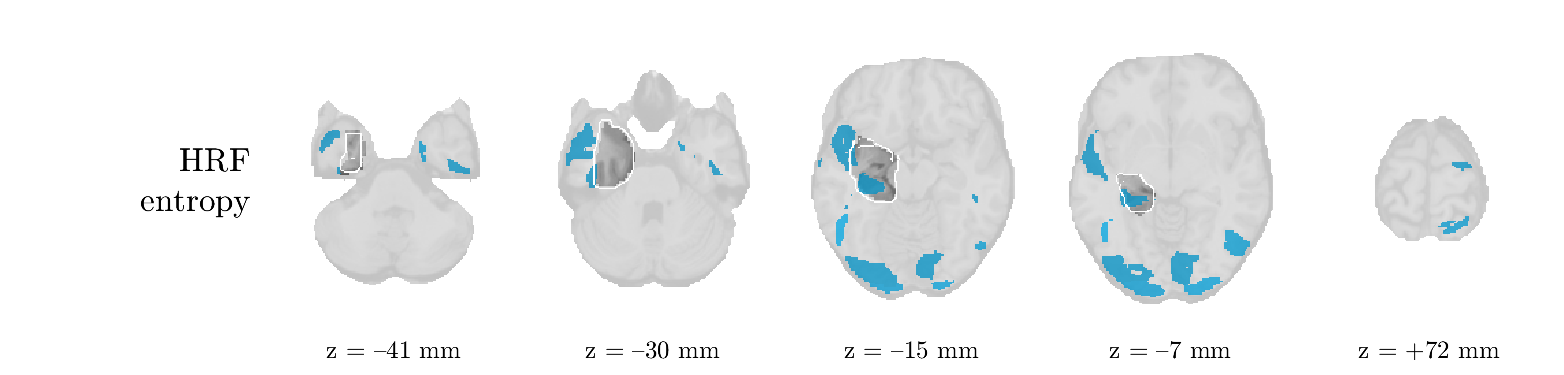

We analyze the solution with sources. Figure 1 shows the EEG signatures and HRF waveforms. One of the sources is highly correlated to the MWF reference (in grey), which was already known from Table B.3. This IED-related source had a typical low-frequency spectrum, which is expected for the typical spike-and-wave interictal discharges. The topography is relatively diffuse, although the highest amplitudes are mostly in the left hemisphere. This is in accordance with the lateralization of ictal onset zone (left temporal lobe, cfr. Table 1). There are some noteworthy observations to be made about some of the other components. The fourth has an unusually sharp spectrum, is mainly localized on two nonadjacent center electrodes, and is sustained for a single period of many seconds Hence, this component likely captured an artifact (of yet unknown origin), although we spotted no large-amplitude changes in the EEG itself. Similarly, the third source is only present at one frontal electrode, and exists in a frequency range above 20 Hz. It might represent a muscle artifact, e.g., due to frowning or twitching of some muscles in the forehead. The HRFs of all ROIs are shown in Figure 1(b). Two of the basis functions seem to have converged to a very similar waveform, which is an unfortunate possibility if two initial HRFs are too close to the same local optimum in their respective parameters. This reduces the expressive power of the basis set, which is clearly visible, since many ROIs have a nearly identical HRF. One of the twenty ROIs with the highest-entropy HRF overlapped the IOZ, although clearly this HRF (bold line) is not among the most dissimilar waveforms for this patient. This is also visible in Figure 2: both the HRF entropy and extremity maps show a small overlap with the delineated IOZ. Despite the good correspondence in the EEG domain, no significant (de)activation of the IED-component is found inside the IOZ.

We analyze the solution with sources, and show the results in Figure 3 and 4. As for patient 1, we found a source which is strongly correlated to the MWF envelope, and which had a mostly low-frequency behavior characteristic for spikes. The topography is mostly uninformative, and does not clearly correspond to the patient’s clinical data. The third source is mostly present at both sides of the head, is very sparsely active in time, and has a high-frequency content: this is most likely an artifact due to the neck muscles. Again, there is one of the highest-entropy HRFs which belongs to a ROI in the IOZ. Now, the waveform is clearly resolved from the other HRFs, through the strong initial dip (before 0 seconds). Such a dip is sometimes observed in HRFs, but its underlying physiological mechanism is not yet fully understood. It is possible that this dip reflects altered vascular autoregulation near the IOZ (cfr. the explanation in the Section 1 of the main text), or a rapid depletion in oxygen due to IED generation (before the IED becomes visible on the EEG). Figure 4 furthermore shows that the IED-related component is significantly active in parts of the IOZ, and deactive in others. As mentioned earlier, this deactivation may or may not be due to errors in sign correction. Interestingly, the ROI with the high alteration in neurovascular coupling is distinct from both the activated and deactivated ROIs.